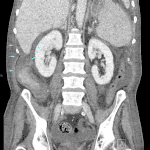

Age: 68

Sex: Male

Indication: Rule out postoperative bile leak, history of TIPS

Radiotracer: Tc99m Mebrofenin

Sample ReportPositive for biliary leak with bile collecting in the right sub-diaphragmatic region and in the right paracolic gutter.